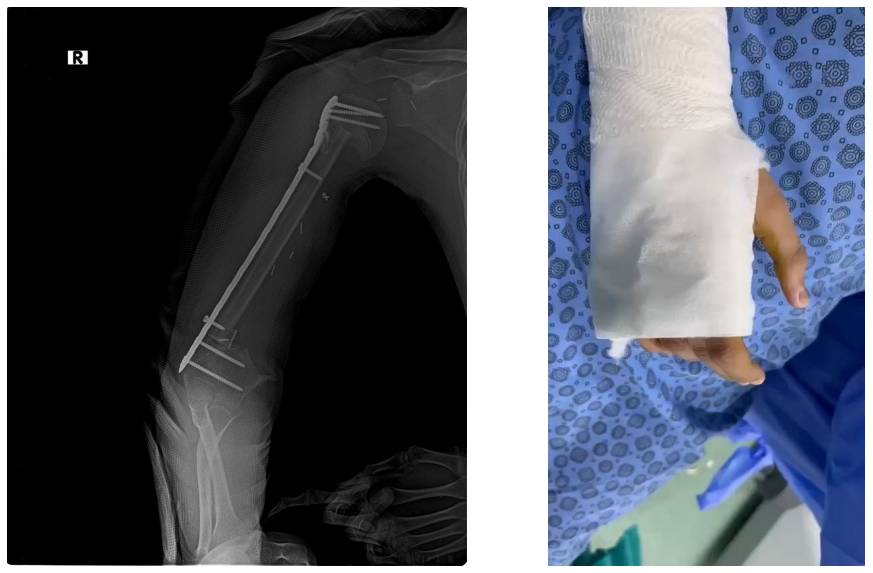

Ameliyat Sonrası: Röntgende rezeksiyon sonrası uygulanan vaskülerize fibulanın uzun anatomik plak ile fiksasyonu ve nörolojik muayenenin doğal olduğunu gösteren video